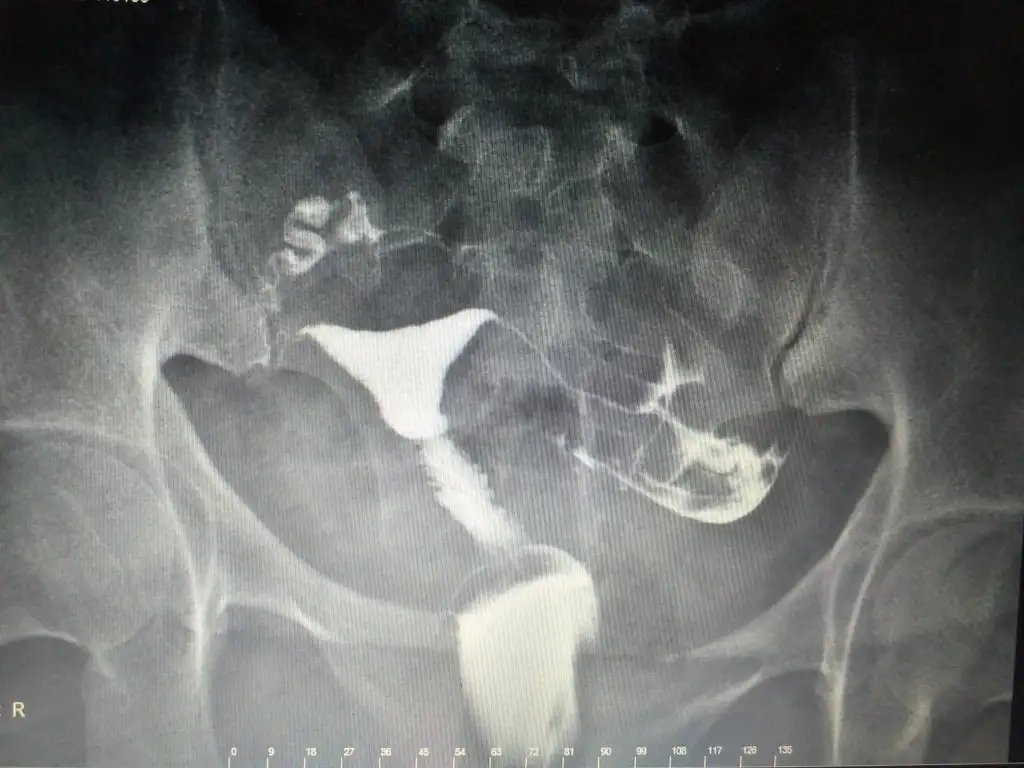

sonuç kagidi yokmuKızlar anlayanlar var mı bundan .

Doktor ne dedi arkadaşım maşallah açık gibi duruyor bir problem varmıydı öncesindeKızlar anlayanlar var mı bundan .

Doktor film sırasında iki tüpte açık sorun yok dedi sonra 20 dakka geçti odasına girdim tekrar bi tüpünden flu geçti diğerinden yavaş geçti ama açık gibi duruyor dedi anlamadımDoktor ne dedi arkadaşım maşallah açık gibi duruyor bir problem varmıydı öncesinde

Yok çekmedi . Film sırasında açık dedi zaten ben anestezi almamıştım hiç acı da duymadım çekilirken . Doktor tüpler açık rahim normal kist miyom yok dedi . 2. Sinde odası çok kalabalık ti geçiştirdi sanki ondan buraya sormak istedimBence iyi durumda gözüküyor yarım saat sonra kontrol için tekrar Röntgen çekti mi

1tanesi normal diğeri biraz yavaş gitmiş gibi ama bu çok sıkıntılı bi durum değil 1 tanesi kapalı bile olsa hamile olabiliyorsunKızlar anlayanlar var mı bundan .

Aşılama yapılabiliyor mu peki bu sonuçla canım1tanesi normal diğeri biraz yavaş gitmiş gibi ama bu çok sıkıntılı bi durum değil 1 tanesi kapalı bile olsa hamile olabiliyorsun

Tabi yapılıyo tek tüp açık olması yeterliAşılama yapılabiliyor mu peki bu sonuçla canım

Çok teşekkür ederim canım . Doktor 2 tüpte açık ama biri yavaş dediğinde bisey anlamadım . Yavaş geçince ne oluyor kiTabi yapılıyo tek tüp açık olması yeterli

Sperm hızla ilerlediğinde hamile olma olasılığın artar çünkü ölmeden rahme yerleşmiş olur . Ayrıca bundan sonrasında hamile kalma olasılık çok fazla özellikle bu ay çünkü tüplerin normalden daha fazla açılmış spermler daha hızlı ilerlemiş olacakÇok teşekkür ederim canım . Doktor 2 tüpte açık ama biri yavaş dediğinde bisey anlamadım . Yavaş geçince ne oluyor ki